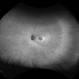

- toxic maculopathy

Clarus 700 - Description

- A 50-year-old woman with a 15 year history of pentosan polysulfate treatment for interstitial cystitis.